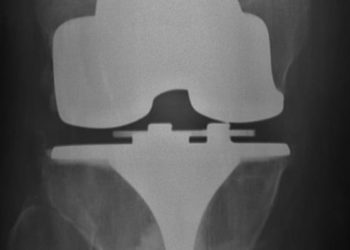

Study Rundown: Bone and joint infections are typically treated with surgical washout and a prolonged course of intravenous antibiotic therapy. Use of intravenous antibiotics has been a long-held standard of care which has significant drawbacks compared to oral treatment, though a thorough comparison has not been conducted recently. The Oral versus Intravenous Antibiotics for Bone and Joint Infection (OVIVA) trial sought to compare oral and intravenous antibiotics for patients with orthopaedic infections. Patients were randomized to oral or intravenous antibiotics after 1 week of starting antibiotic therapy. There was no significant difference in the primary outcome of treatment failure at 1 year between the oral and intravenous antibiotic groups. Incidence of serious adverse events was also similar between treatment groups.

In-Depth [randomized controlled trial]: This multicenter, open-label, randomized controlled trial enrolled patients between 2010 and 2015. Eligible participants had osteomyelitis, a native infected joint, or an infected prosthetic/orthopaedic fixation device. If patients were surgically treated, randomization to oral or intravenous groups occurred within 7 days of surgery. Patients were treated for 6 weeks after randomization, and extended antibiotic treatment was also possible if clinically warranted. If no surgery was required, randomization occurred within 7 days of beginning antibiotics. Choice of antibiotics was left to the guidance of treating physicians. Participants in the oral (n=466) and intravenous (n=443) groups were followed for 1 year to assess for the primary outcome of treatment failure, which showed oral therapy to be noninferior to intravenous therapy (13.2% vs 14.6% failure for oral and intravenous groups, respectfully; difference in risk, -1.4%; 95% confidence interval [CI], -5.6 to 2.9). Intention-to-treat and per-protocol analysis supported the conclusion of oral therapy as noninferior. Patients in the intravenous group more commonly discontinued their treatment. Patients in the intravenous group also experienced longer hospital stays and had significantly more complications with intravenous catheters. Serious adverse events occurred at similar rates in the two groups (26.2% and 27.7% for oral and intravenous groups, respectively; P=0.58). Incidence of C. difficile diarrhea was similar in the two groups.